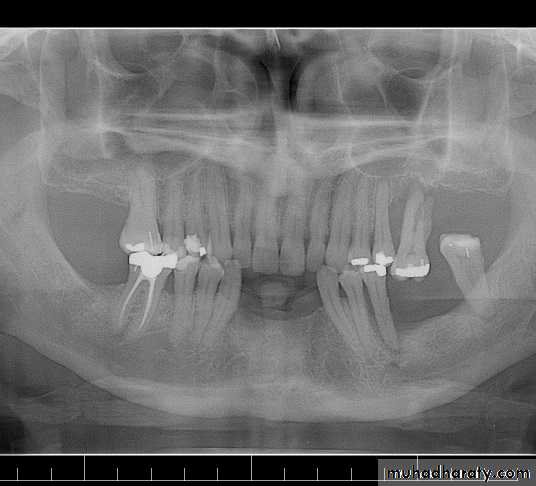

Radiographs

1-areas of infection and other pathologies .2-the presence of root fragments, foreign objects, bone spicules and irregular ridge formations.

3-the presence and extent of caries and the relation of carious lesions to the pulp and periodontal attachment .

4-evaluation of existing restorations : evidence of recurrent caries, marginal leakage, and overhanging gingival margins.

5-the presence of root canal fillings .

6-evaluation of periodontal conditions present .

7-to evaluate the alveolar support of abutment teeth, their number, the supporting length and morphology of their roots.

8-the relative amount of alveolar bone loss suffered through pathogenic processes, and the amount of alveolar support remaining.